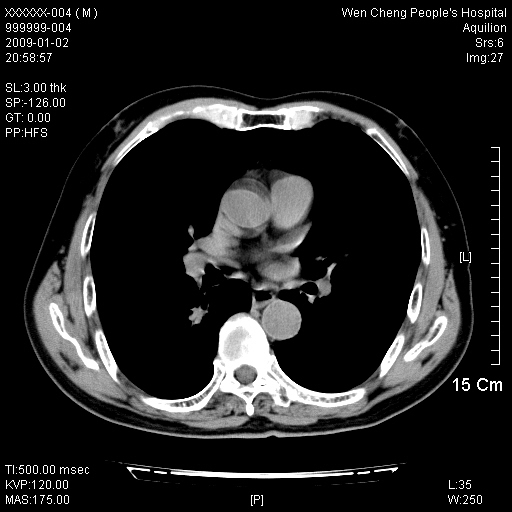

男性,73岁,有慢支病史,肿瘤系列标志物检验正常,血沉及血常规正常

右肺下叶背段小片状 磨玻璃样模糊影,内见血管及含气支气管像,支气管管壁增厚。考虑:慢性炎症!

右肺下叶背段小片状 实性与磨玻璃样影,内见血管及含气支气管像,支气管管壁增厚,边缘见长毛刺影。考虑:慢性炎症或肿瘤!建议抗炎治疗复查,密切观察随访!

右肺下叶片团状影内见扩张的含气支气管和支气管管壁增厚,其周有磨玻璃样模糊影和长毛刺。考虑慢性炎症可能性大。

2、右肺下叶片团状影内见扩张的含气支气管和支气管管壁增厚,其周有磨玻璃样模糊影和长毛刺。考虑周围型肺ca可能,结核不排。

高度提示细支气管肺泡癌,建议抗炎治疗半月观察病灶变化,如无明显改变,建议立即手术治疗.

病变形态非常不好呀,临床上血常规及症状也不明显,不太支持炎性病灶,高度警惕肿瘤病变,最好做个纤支镜检查。